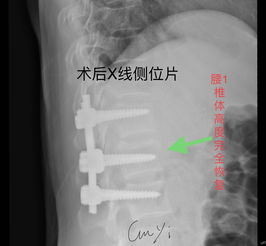

胸腰椎前路內(nèi)固定技術(shù)的應(yīng)用使病灶得到清除、脊髓獲得減壓、脊柱得到即刻穩(wěn)定,這樣一方面為病人術(shù)后早期離床活動(dòng)、早期康復(fù)提供了可能性,另一方面也為神經(jīng)功能的保護(hù)或恢復(fù)創(chuàng)造了必要條件;其合理性和臨床效果逐步得到了公認(rèn)。 但前路手術(shù)無(wú)法探查脊髓、馬尾損傷的情況并給于必要的處理,因此把握好前路手術(shù)的適應(yīng)證是臨床取效的關(guān)鍵,以下幾點(diǎn)基本達(dá)成共識(shí):胸腰椎骨折或骨折脫位伴不全癱,確證在硬脊膜前方有壓迫存在;經(jīng)過(guò)脊髓造影、MRI或臨床神經(jīng)學(xué)體征可判斷,除硬膜前受壓外,馬尾、脊髓本身并無(wú)需探查及修復(fù)時(shí),必須致力于前路減壓;脫位已超過(guò)2~3周者,后路手術(shù)已難以復(fù)位者;若伴不全癱需行減壓術(shù),亦宜選用前路減壓。

例如爆裂型骨折存在下述3種情況時(shí),就需行前路減壓術(shù):1.合并嚴(yán)重神經(jīng)系統(tǒng)癥狀,或伴有進(jìn)行性神經(jīng)功能惡化的;2.就診較晚已超過(guò)2周以上者;3.脊柱CT掃描斷層顯示已有較大的骨折片突入椎管內(nèi),使椎管變窄超過(guò)30%以上,預(yù)示后縱韌帶已有明顯損傷,使用后路手術(shù)方法,已無(wú)法使骨折片復(fù)位;4.無(wú)神經(jīng)壓迫癥狀,椎管壓迫超過(guò)50%,需要對(duì)畸形進(jìn)行矯正者。 胸腰椎骨折在臨床上較多見(jiàn),如果護(hù)理不當(dāng), 會(huì)給患者造成終生殘疾。